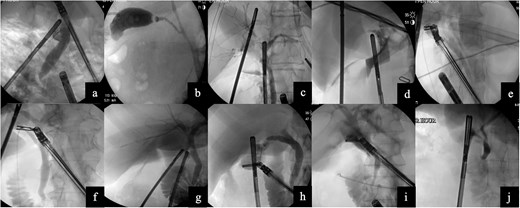

Images from intraoperative cholangiograms—(a) Case 1, (b) Case 2, (c) Case 3, (d) Case 4, (e) Case 5, (f) Case 6, (g) Case 7, (h) Case 8, (i) Case 9, and (j) Case 10.

A 48-year-old female with cholelithiasis presented to the emergency department (ED) complaining of a 1-day history of mild, constant abdominal pain associated with nausea and vomiting. On physical exam, she had moderate right upper quadrant and epigastric tenderness. Ultrasound revealed cholelithiasis with an impacted calculus in the neck of the gallbladder and a dilated CBD of 10 mm. The decision to forgo MRCP was made. Instead, the patient underwent a robotic laparoscopic cholecystectomy with ICG and IOC. The cholangiogram did not show any filling defects (Fig. 2a). She was seen in the office ~2 weeks later and made an uneventful recovery.

A 55-year-old obese male presented to the ED complaining of sudden-onset midsternal and epigastric abdominal pain that radiated to his back. Labs revealed a leukocytosis of 16.5, lipase of 27 679, aspartate aminotransferase (AST) of 124, and alanine aminotransferase (ALT) of 114, alkaline phosphatase (alk phos) of 93, and a total bilirubin level of 1.3. The patient was initially not optimized for a surgical procedure and had a cholecystostomy tube placed. Subsequently, he underwent a robotic cholecystectomy with ICG, IOC, removal of the cholecystostomy tube, and Blake drain placement. The cholangiogram was negative for any filling defect (Fig. 2b). The patient tolerated the procedure without any issues and was discharged home. He made an uneventful recovery.

The patient was an 84-year-old female who presented to the ED with sharp, epigastric abdominal pain. Labs revealed a leukocytosis of 12.5, lipase of 13 365, AST of 702 and ALT of 491, alk phos of 56, and a total bilirubin level of 2.1. Ultrasound revealed cholelithiasis. The patient underwent a robotic cholecystectomy with ICG and IOC. The cholangiogram did not show any filling defects (Fig. 2c). The patient tolerated the procedure without any issues and was discharged home.

A 24-year-old female with morbid obesity presented to the ED with right upper quadrant abdominal pain. Labs were significant for leukocytosis of 12.3. Ultrasound revealed cholelithiasis and a dilated CBD of 8 mm. The patient underwent a robotic cholecystectomy with ICG and IOC. The cholangiogram showed a sharp cut-off shortly after the cystic duct, suspicious for a stone at the confluence of the cystic duct and CBD (Fig. 2d). Postoperative ERCP revealed sludge in the CBD. Complete removal was accomplished by biliary sphincterotomy and balloon extraction. Post-sphincterotomy cholangiogram was normal. The patient was discharged and seen in the clinic 2 weeks later and made an uneventful recovery.

The patient was a 51-year-old female who presented to the ED with persistent postprandial right upper quadrant abdominal pain. Labs were remarkable for AST of 293 and ALT of 206. Ultrasound was equivocal for acute cholecystitis and revealed an intraluminal filling defect. She underwent a robotic cholecystectomy with ICG and IOC. The cholangiogram showed proper retrograde filling of the left and right hepatic ducts and adequate anterograde visualization of the CBD (Fig. 2e). The patient was discharged and made an uneventful recovery without the need for an ERCP.

The patient was a 61-year-old obese female who presented to the ED with a 1-day history of constant right upper quadrant pain associated with nausea and vomiting. Labs revealed a leukocytosis of 16.9, lipase of 11 211, AST of 125, ALT of 123, alk phos of 131, and total bilirubin level 0.7. Ultrasound revealed cholelithiasis and sludge. Computer tomography of the abdomen and pelvis revealed mild diffuse peripancreatic edema, suspicious for acute pancreatitis. Patient underwent robotic cholecystectomy with ICG and IOC. Cholangiogram revealed CBD dilation but no stones (Fig. 2f). She was seen two weeks later in the office and made an uneventful recovery.

The patient was a 35-year-old male with cholelithiasis who presented with a 5-day history of right upper quadrant abdominal pain. Labs were remarkable for a mild elevation of the ALT at 73. Ultrasound revealed cholelithiasis and a CBD of 5.8 mm. Patient was taken for robotic-assisted laparoscopic cholecystectomy with ICG and IOC. IOC was negative for any filling defects or strictures (Fig. 2g). Patient was discharged and recovered well with no complications.

The patient was a 22-year-old female with cholelithiasis who presented with 2 months of intermittent nausea and epigastric pain. Previous ultrasound revealed a contracted gallbladder with cholelithiasis and a CBD of 6.8 mm. Labs were remarkable for AST of 210 and ALT of 188. Patient was taken for robotic cholecystectomy with ICG and IOC. IOC was negative for any filling defects or strictures and showed contrast draining into the duodenum (Fig. 2h). Patient was discharged and was seen a week later for postoperative visit; she recovered well with no complications.

The patient was a 38-year-old female who presented to the ED with a 1-day history of abdominal pain with associated nausea and vomiting. Ultrasound was suspicious for acute cholecystitis and the CBD was 5.86 mm. Patient underwent robotic-assisted laparoscopic cholecystectomy with ICG and IOC. IOC was negative for filling defects, strictures, and showed contrast in the duodenum as well as the hepatic ducts (Fig. 2i). Patient was discharged postoperatively and was seen 2 weeks later for a postoperative visit; she recovered well with no complications.

The patient was a 67-year-old female with a recent hemorrhagic stroke who presented with a 1-week history of abdominal pain and was found to have gallstone pancreatitis. The medicine team ordered an MRCP which revealed cholelithiasis with gallbladder wall thickening without any evidence of biliary dilatation or CBD stones. She underwent robotic cholecystectomy with ICG and IOC. IOC was negative for filling defects (Fig. 2j). Patient recovered uneventfully.